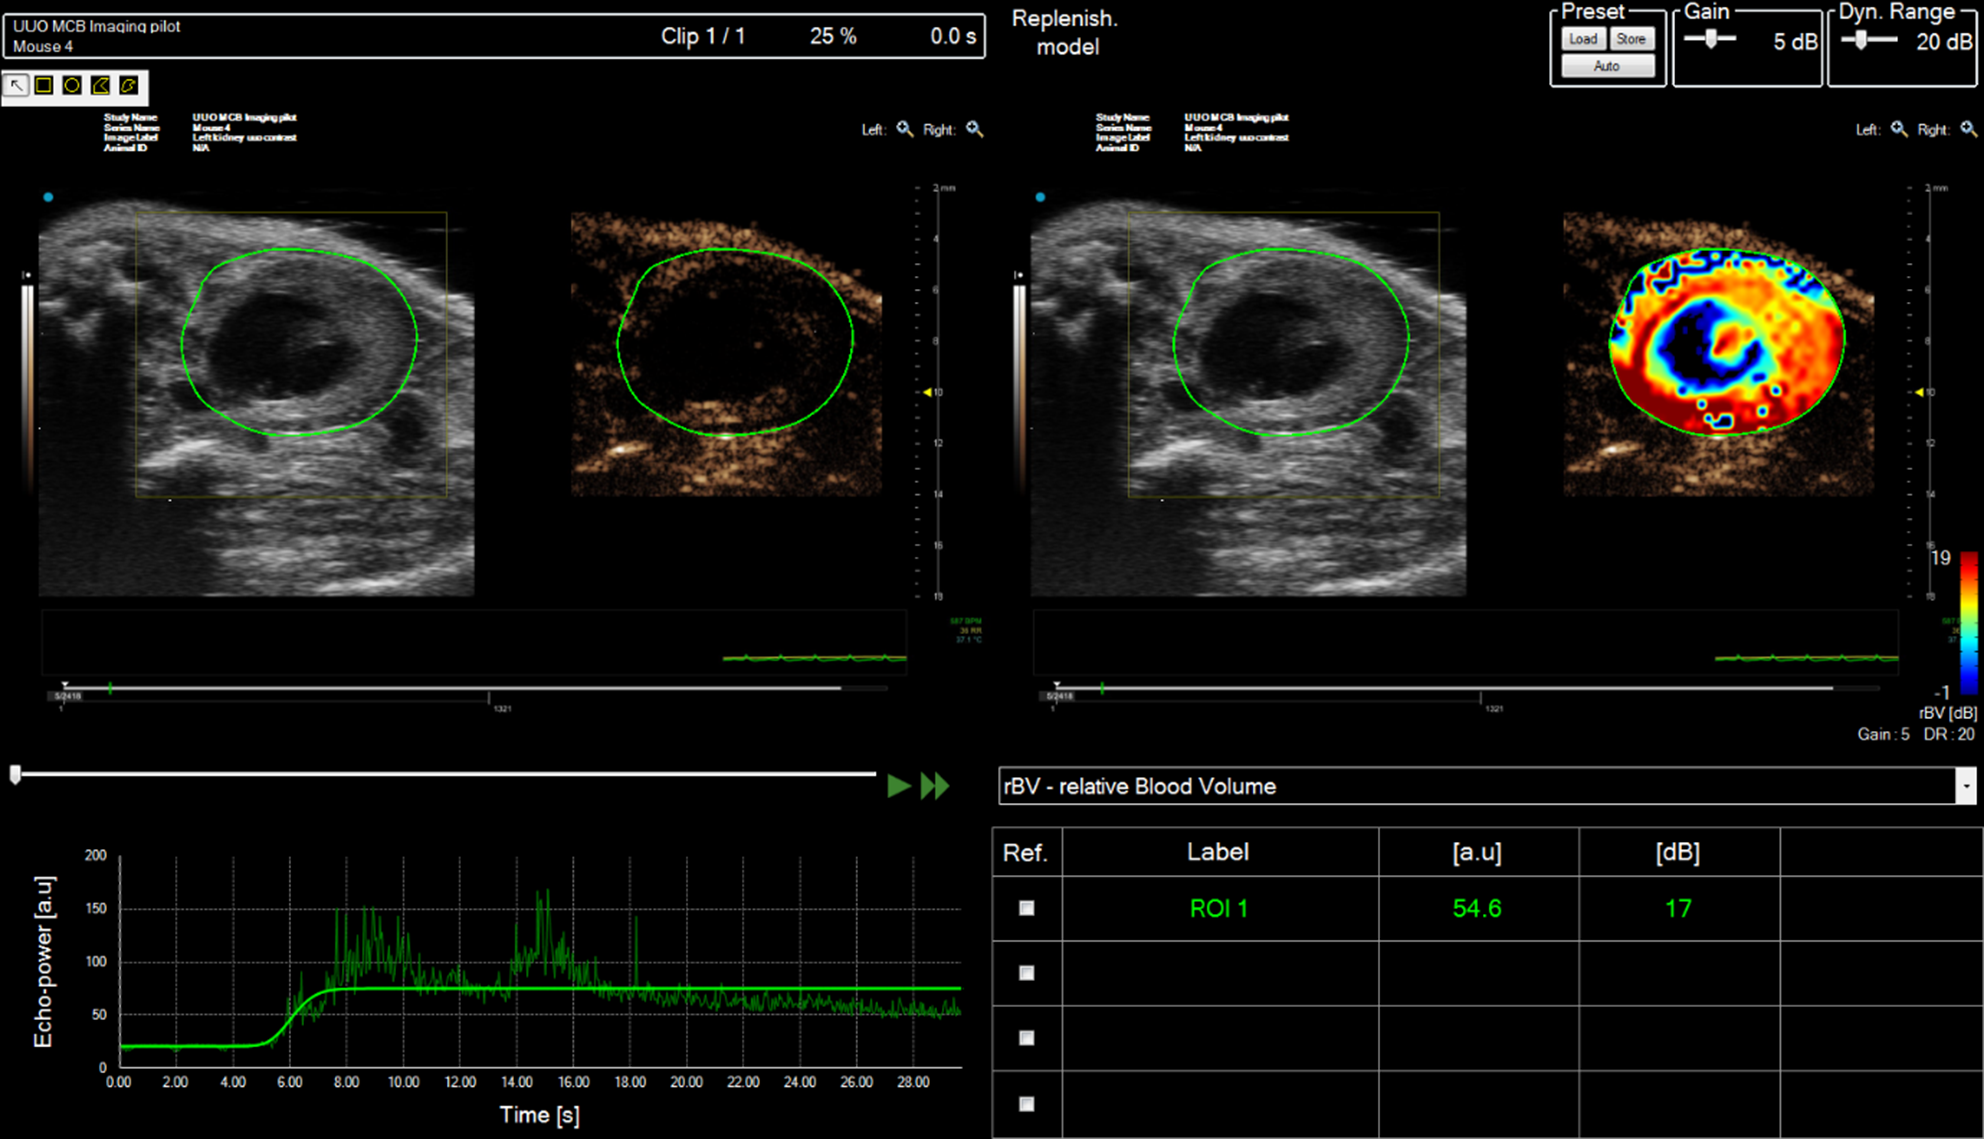

Non-linear imaging techniques are utilized principally in the detection of ultrasonic contrast microbubbles (encapsulated gas bubbles). Contrast microbubbles when insonated with an ultrasound beam will begin to oscillate, expanding during the negative phase of the cycle and contracting during the positive phase. Dependent on the frequency and amplitude of the transmitted ultrasound the microbubbles can produce a significant non-linear backscattered signal without being destroyed. Since soft tissues predominantly scatter ultrasound in a linear manner by removing or canceling the linear component of the backscattered signal the kinetics and dynamic enhancement of organs can be visualized and quantified by measuring the increase in non-linear signal as a function of time. This can then be displayed in a variety of ways such as a maximum intensity projection sequence which will enable the dynamic filling patterns to be established within a region or as a graph illustrating the backscattered intensity kinetics within a region-of-interest (Figure 9).

FIGURE 9

www.frontiersin.org

Figure 9. Contrast analysis of data-set acquired from right mouse kidney post ischemia-reperfusion (IRI) injury after tail-vein bolus injection of SonoVue. Mouse scanned in prone position. Multiple regions of interest (ROIs) can be drawn onto the image and the enhancement can be tracked as a function of time (bottom LHS). The relative enhancement of each ROI relative to pre-contrast image can be calculated and color-encoded (Top RHS).

Vascularity of the kidney can also be studied using ultrasonic contrast agents. When contrast is being used, the mouse is scanned in the prone position avoiding the potential of imaging artifacts caused by intestinal shadowing which can occur when the kidneys are scanned with the mouse in the supine position. Contrast agents are bolus-injected or infused using a syringe pump via the tail-vein. An injection of 50 μl Micromarker (Bracco Research SpA, Geneva, Switzerland) over a 5 second period of a 1:5 dilution is a typical dosing regimen. For acquisition, baseline images are acquired in contrast-specific imaging mode immediately prior to injection of the contrast agent and are saved either as a separate data-set or a temporal stamp is placed on the contrast image sequence indicating when contrast is injected and images taken prior to this time-stamp are considered baseline images. An alternative approach is to inject the contrast agent, then destroy the contrast agent within the 2D plane using a short, low-frequency high pressure acoustic pulse. The low-pressure contrast-specific imaging sequence is then reinstated, with the initial frames immediately after these high pressure pulses regarded as baseline images with subsequent frames displaying contrast enhancement. After contrast injection a long sequence of 2D images are obtained, the length of sequence can be pre-set by the user. Once the sequence has been saved, either in-house software or contrast-specific software developed by the manufacturers can be used to map the intensity of the backscattered signal within the regions-of-interest (eg medulla, cortex) to study the perfusion-dynamics. Metrics of interest include area-under-the curve, time-to-peak enhancement, wash-in rate and these can be used as indicators of blood volume and vessel density [20]. In many instances if an ischemic-reperfusion-injury (IRI) mouse model is being studied, one kidney can act as a control and both B-mode and contrast-enhancement data can then be acquired from both kidneys.